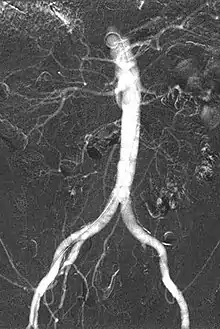

Carbon dioxide angiography is a diagnostic radiographic technique in which a carbon dioxide (CO2) based contrast medium is used - unlike traditional angiography where the contrast medium normally used is iodine based – to see and study the body vessels.[1] Since CO2 is a non-radio-opaque contrast medium, angiographic procedures need to be performed in digital subtraction angiography (DSA).

The CO2 does not mix with blood. At atmospheric pressure CO2 is in gaseous form and, when it comes out from the catheter, it forms a train of bubbles which displaces blood, causing a transient ischemia, in relation to the bloodstream (systolic pressure). When added together by DSA “stacking” software,[5] the result is a composite diagnostic image of the frames.